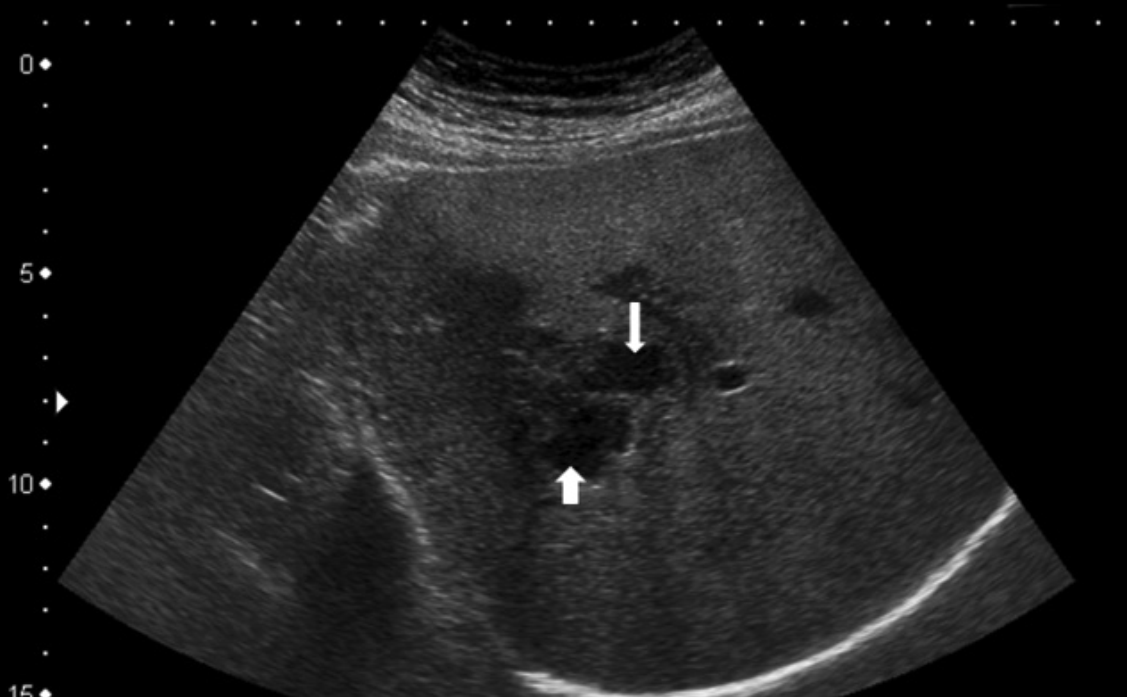

Hai thai phụ nhập viện với tình trạng đau bụng thượng vị tăng dần kèm sốt và buồn nôn. Công thức máu có tình trạng tăng bạch cầu ái toan và xét nghiệm huyết thanh chẩn đoán Fasciola spp. dương tính. Siêu âm ghi nhận ổ áp xe ở gan.

Một số trường hợp, ấu trùng sán di chuyển lạc chỗ và gây tổn thương thành ruột, màng phổi, cơ thăn,… Xét nghiệm máu có thể phát hiện tăng bạch cầu ái toan. Siêu âm bụng có thể thấy các tổn thương ở gan.

Giai đoạn sán trưởng thành ở ống mật, kéo dài nhiều năm: Người bệnh thường sốt, ăn không ngon. Một số người bị biến chứng tắc nghẽn đường mật có triệu chứng vàng da, sốt, đau bụng từng cơn. Siêu âm bụng phát hiện một khối mềm sáng gây tắc nghẽn đường mật ngoài gan.